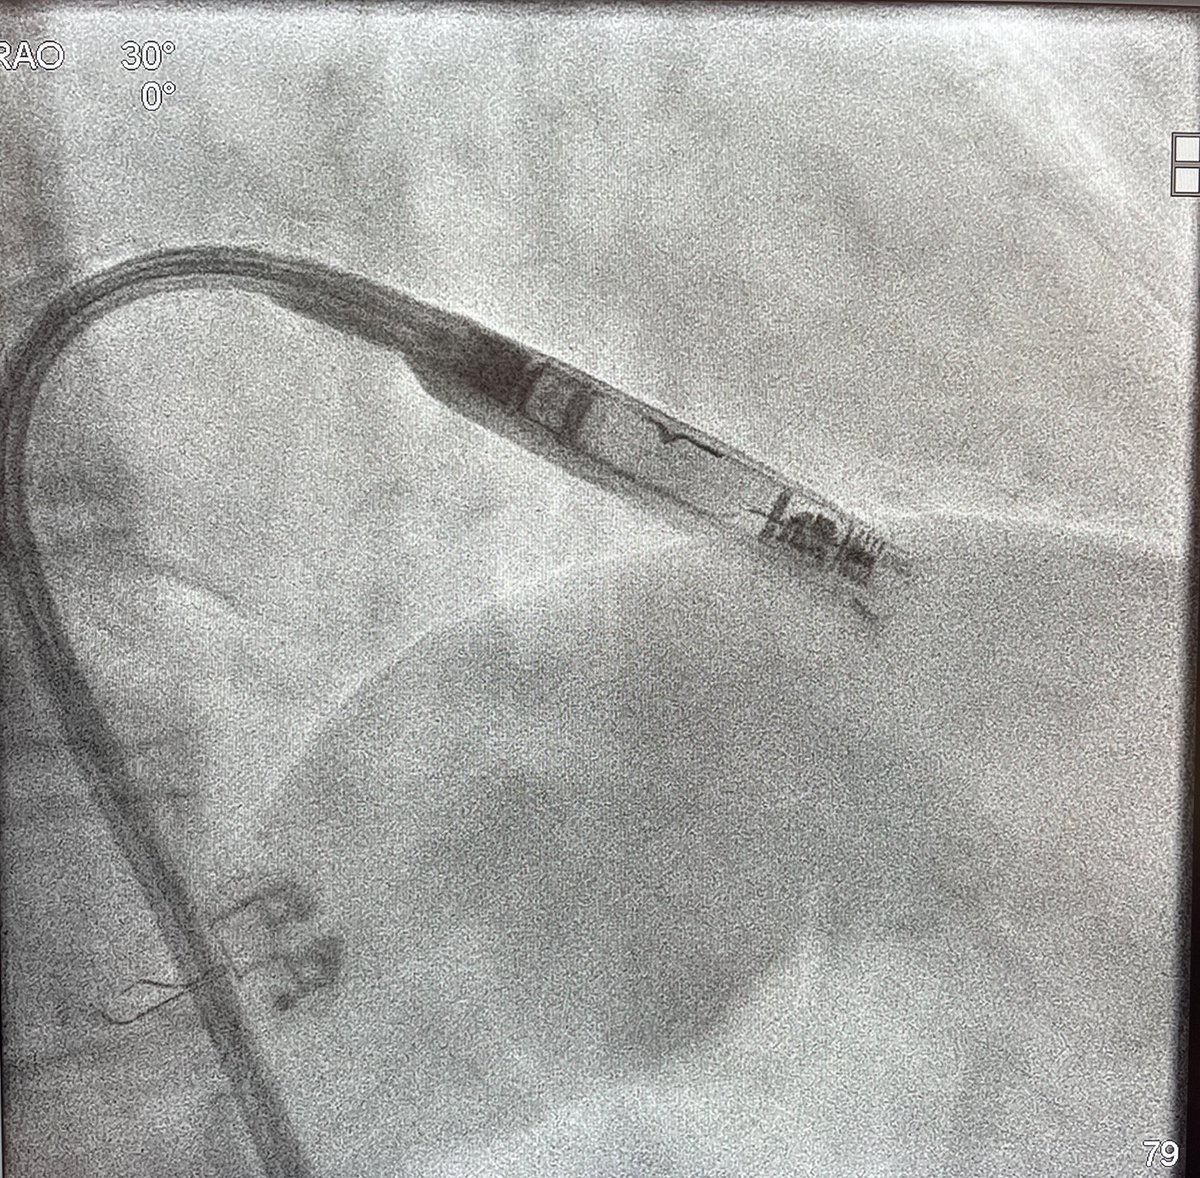

Excited to be the first hospital system in Illinois to implant the new AVEIR leadless pacemaker. What a great and exciting technology that will benefit our patients. We implanted 3 #AVEIR today. #forwardtogether @NorthShoreWeb @SwedishChicago @AbbottCardio @AbbottGlobal

HanyDemo's tweet image. Excited to be the first hospital system in Illinois to implant the new AVEIR leadless pacemaker. What a great and exciting technology that will benefit our patients. We implanted 3 #AVEIR today. #forwardtogether @NorthShoreWeb @SwedishChicago @AbbottCardio @AbbottGlobal